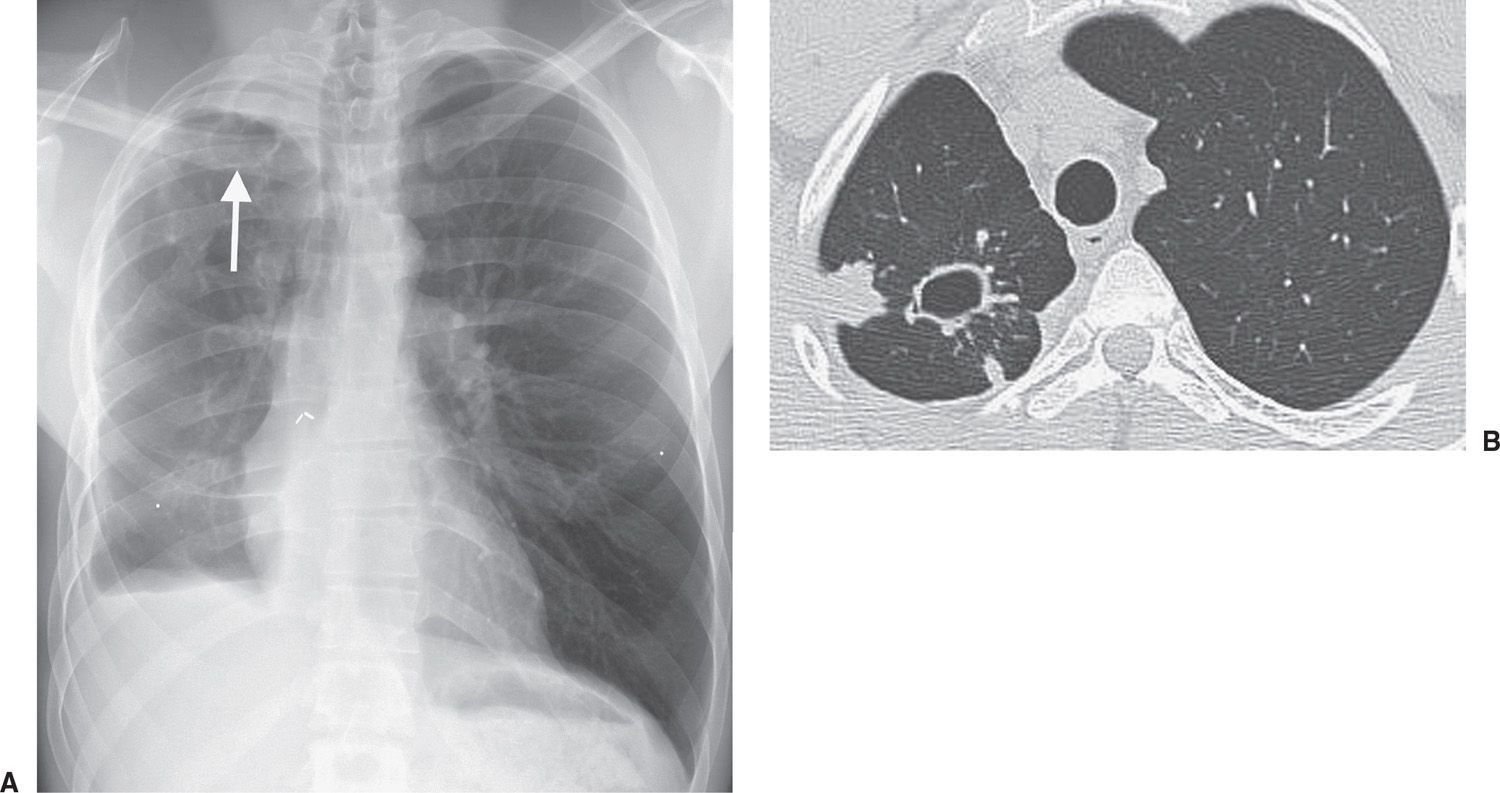

Figure 2 from Diagnostic Accuracy of Chest Radiography for the

Figure 2 from Diagnostic Accuracy of Chest Radiography for the Does Chest X Ray Show Latent Tb A positive test result for tb infection means you have tb germs in your body. Should consider treatment for latent tb infection to prevent tb disease. Have typically normal chest radiographs. A positive test indicates you. Your health care provider will do other tests to determine if you have inactive tb or active tb. The world health organization published guidelines. Does Chest X Ray Show Latent Tb.